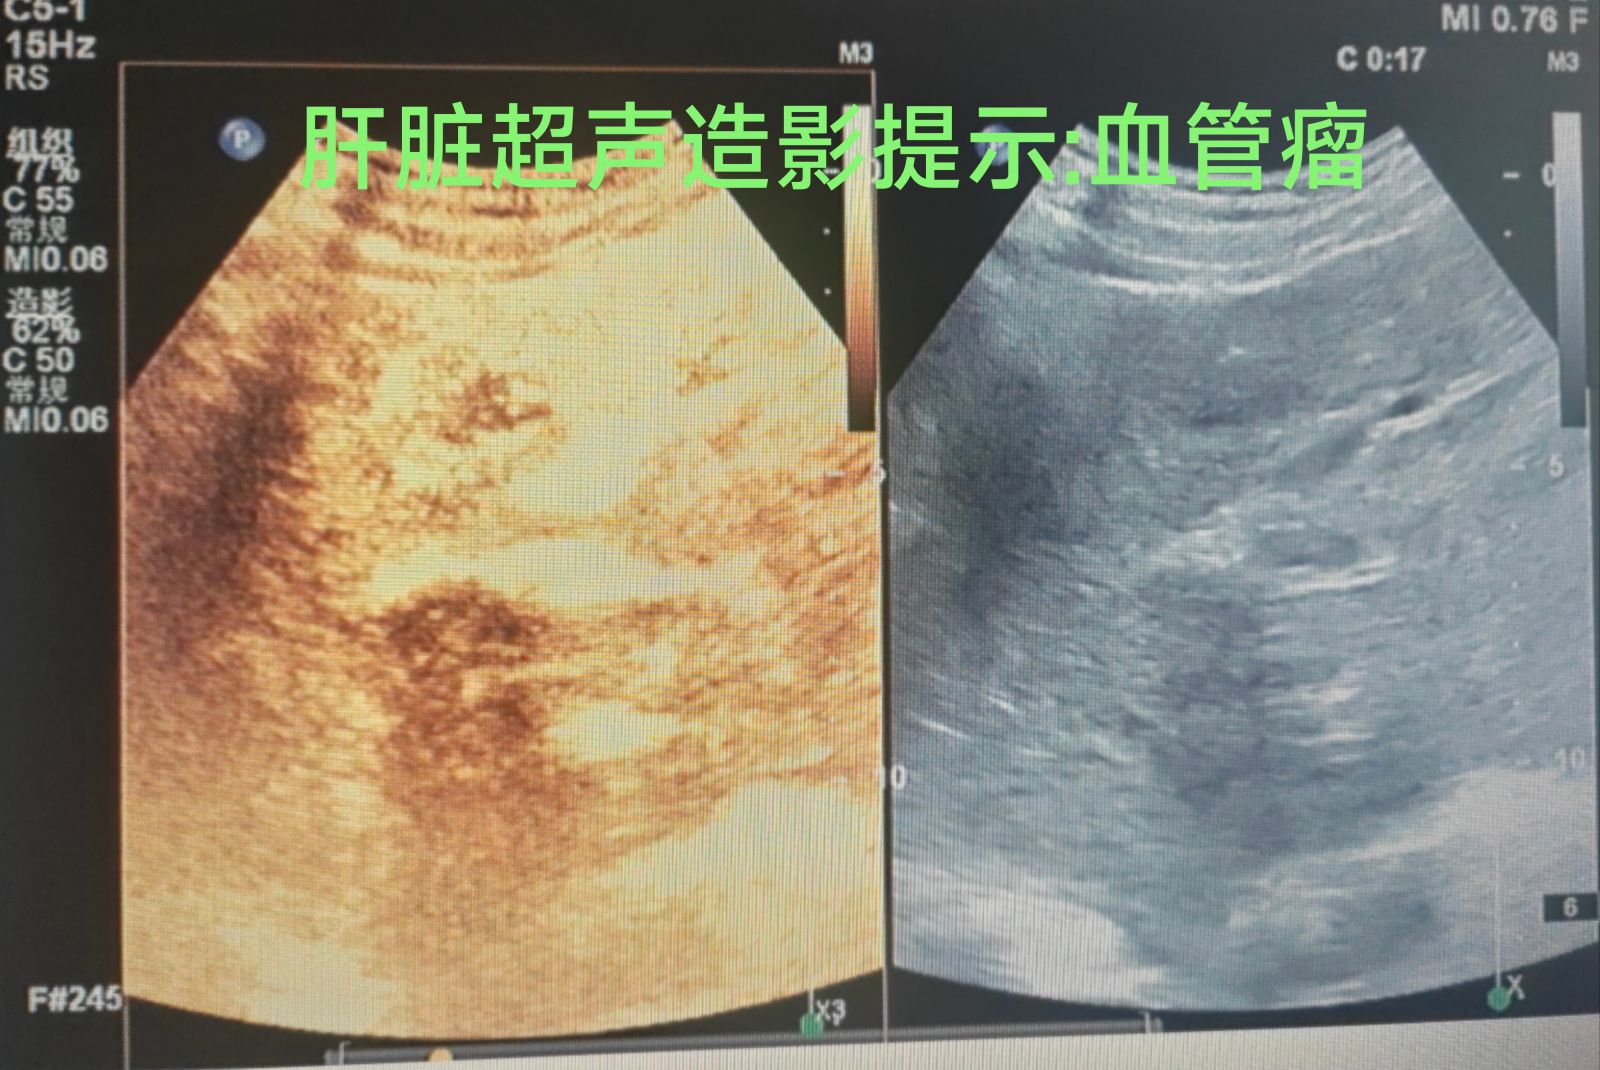

当传统影像检查遭遇诊断盲区,当患者担忧辐射与创伤风险时,超声造影凭借其革命性的“零辐射、高分辨率、实时动态成像”技术,正重塑精准诊断格局。它如同为影像诊断装上“微泡之眼”,使毫米级的隐匿病灶清晰显现,引领医学进入一个更安全、更精准的“透明诊断时代”。

超声造影剂使血管网络与组织灌注实施显影,实现血液动力学全程可观、可视,微循环灌注定量分析,可早期捕捉3mm以下的病灶。

1.肿瘤筛查:肝癌、乳腺癌、甲状腺癌等疾病的早期定性,避免过度穿刺,确诊时间提前6-12个月。